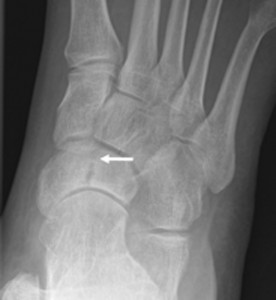

Συμπτώματα κατάγματος στο σκαφοειδές οστό

Στο κάταγμα του σκαφοειδούς σπάνια υπάρχει πρήξιμο. Οι περισσότεροι ασθενείς που παρουσιάζονται με κάταγμα σκαφοειδούς παραπονιούνται για ένα θρομβώδη πόνο στο εσωτερικό άκρο του ποδιού, ο οποίος αυξάνεται κατά την άσκηση και ελαττώνεται με ξεκούραση χωρίς να υποχωρεί τελείως.